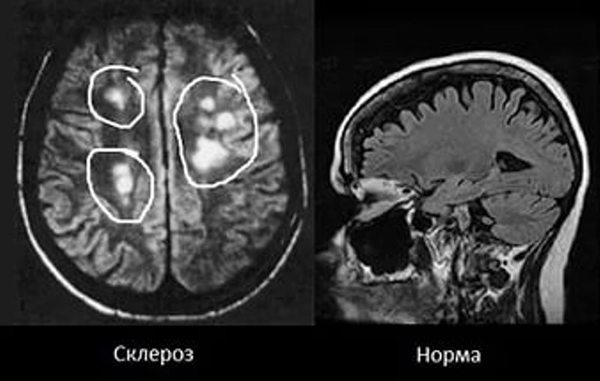

Мне сделали МРТ с контрастированием (в вену укол делается с жидкостью, которая безвредна и ярче покажет места на снимке), и врачи обнаружили у меня большое количество очагов.

Очаг - светлое пятно, которого не бывает у здорового человека. Как можете заметить, пятна рассеяны по мозгу, оттого и название содержит слово рассеянный. Это не мой снимок, у меня очагов было 20-30, не помню точно уже..

Когда возникают обострения - пятен больше и они крупнее, когда идёт спад - пятен меньше и они мельче.